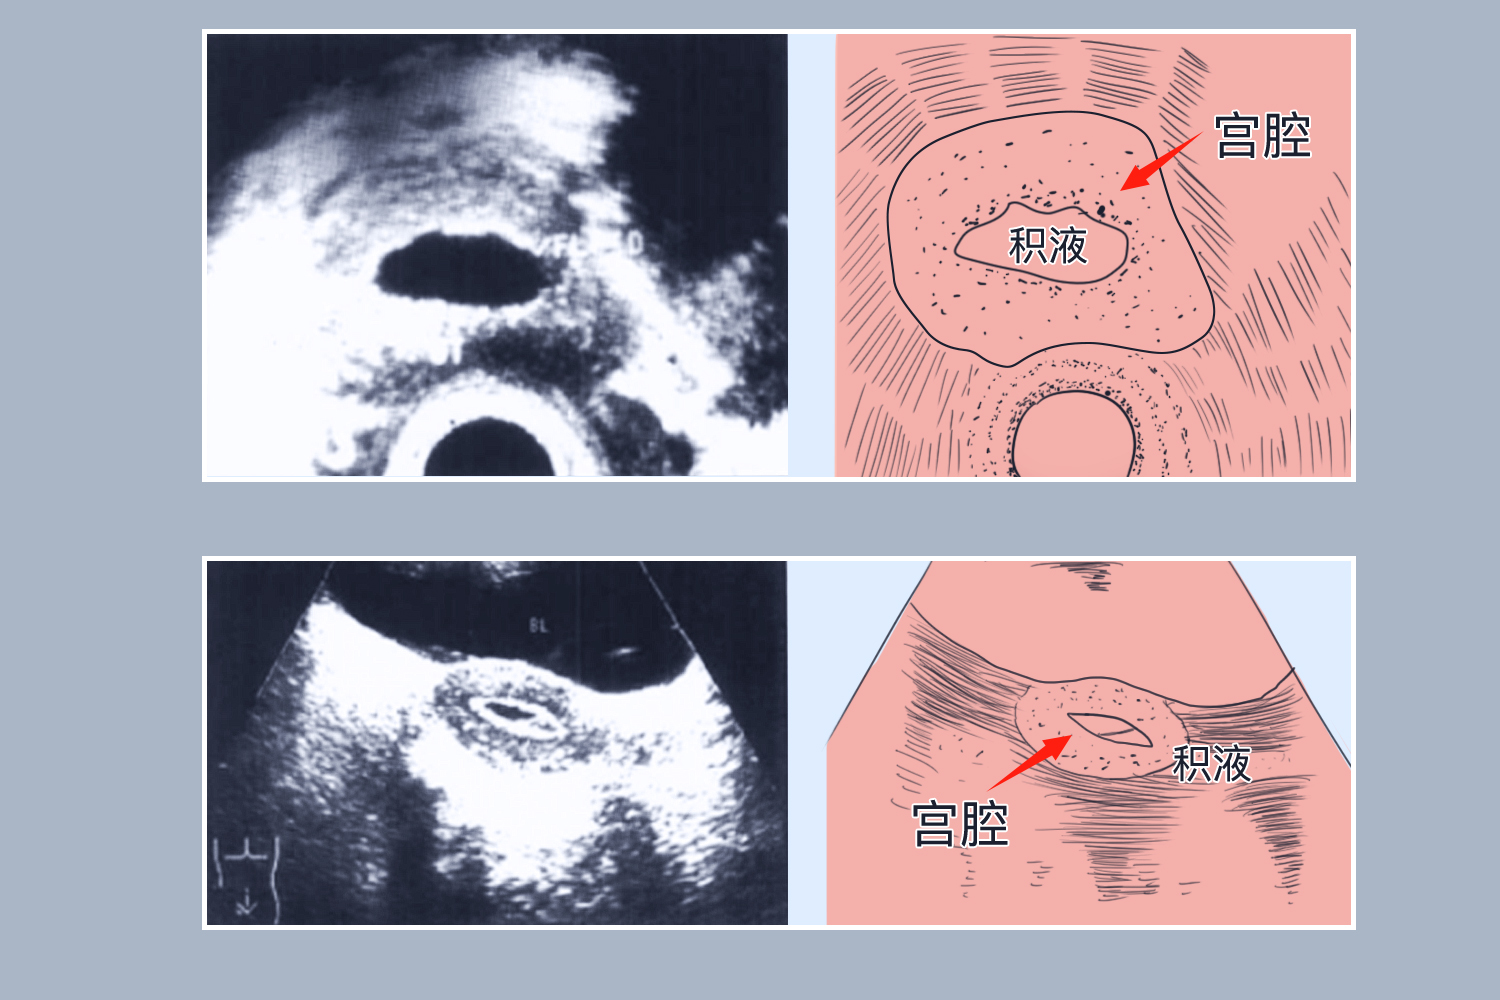

宫腔分离5mm伴宫腔积液是否严重,取决于其诱发因素。生理性可自愈,炎症需抗感染,手术创伤要处理,恶性病变需活检。

3、手术创伤:刮宫术、宫腔镜手术等宫腔操作后,可能会引起宫腔粘连或损伤,导致积液和宫腔分离,如果处理不当,可能会影响子宫内膜的恢复和生育功能,需要根据具体情况进行治疗,如使用促进子宫收缩的药物、预防粘连的措施等。

4、恶性病变:子宫内膜癌等恶性肿瘤可能导致宫腔内出现积液和宫腔分离,除了宫腔分离,患者可能会有不规则阴道出血、消瘦等症状,需要进行病理活检等进一步检查以明确诊断,并制定相应的治疗方案。